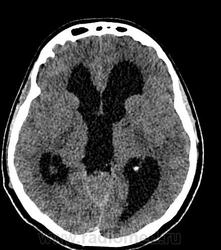

Девушка 30 лет. Поступила с диагнозом Эпилепсия. Неоднократные синкопы, начавшиеся после родов. Роды в начале марта, все благополучно. После родов, как-то так плохо все,шатает, голова болит. Через месяц обратилась в республиканскую больницу, выполнена кт- смешання гидроцефалия. Пролечили и выписали с диагнозом Дистония. Как-то так.

-признаки интравентрикулярной окклюзи выходных отверстий 4 желудочка, с резким расширением всех отдела желудочковой системы.

-резкое сужение охватвающей и большой цистерн

-выраженное расширение хиазмальной и предпонтийной цистерн

-межполушарная,латеральные щели и субарахноидальные пространства значительно уменьшены в объеме за счет увелиения желудочков и отека мозга

-истонены кости основания черепа,усилен рельеф внутренних костных пластин,углублено и расширено турецкое седло,опускание СЧЯ

-ствол и продолговатый мозг в дорсальном отделе уплощены,смещены вентрально

-в полости 4 желудочка объемное образование с учсатками кровоизлияния, с распространением каудально, признаки вклинения миндалин в БЗО,большая цистерна и САП кранио-вертебрального перехода не прослеживаются.